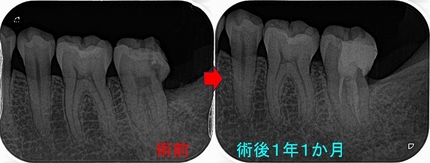

術後1年のレントゲンを撮りに来てくれましたので口腔内写真も撮らせてもらいました。

2026 EEdental TAY (3).jpg

2026 EEdental TAY (4).jpg

問題無く経過しており、綺麗に残せて良かったです!